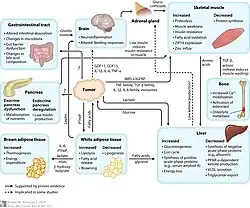

The way cachexia works is not well understood, but research suggests it is linked to inflammation, changes in metabolism, and hormone changes in the body.[5]

Inflammatory

Certain molecules in the body, called Inflammatory cytokines, play a big role in causing cachexia. Two important ones are tumor necrosis factor (TNF) and interleukin 6 (IL-6).[6]

Tumor necrosis factor (TNF)

TNF breaks down muscle and fat while stopping new muscle and fat cells from forming by activating the ubiquitin proteasome pathway.[5][6][17][18][19][20] It also triggers the release of other cytokines that also speed up muscle loss. Since this process is very complex, cachexia is unlikely to be caused by one molecule.[18] While it is thought to be produced by immune cells called macrophages, scientists are still unsure of exactly where TNF is produced in cachexia.[6]

Interleukin-6 (IL-6)

IL-6 is thought to cause muscle loss by starting a pathway called the JAK/STAT pathway.[5][6][20][21] IL-6 is produced by immune cells called macrophages, potentially producing acute phase reactants which may worsen muscle loss.[6][18]

Other molecules may include:

- Myostatin - Prevents muscle growth and is often higher in people with cancer.[6][18][22]

- Activin - May contribute to muscle loss when TNF is also active.[6][18]

- Growth Differentiation Factor 15 (GDF-15) - Normally produced during cellular stress. Thought to play a role in food aversion and is associated with reduced food intake.[5]

Metabolic

Cachexia can also result from changes in metabolism. Tumors sometimes release molecules that break down fat and muscle, causing cachexia by making it harder for the body to keep up with energy needs.[19] These molecules include lipid mobilizing factor, proteolysis-inducing factor, and mitochondrial uncoupling proteins.[19][23] In addition, uncontrolled inflammation in people with cachexia increases the body's need for nutrients.[20][22]

The way the body uses nutrients is also changed in cachexia. People with cachexia can have loss of appetite, are less responsive to insulin, and can have increased fat breakdown, all of which make it difficult for the body to properly use food. This is especially true in people with cancer.[18]

Hormonal

Hormones are signaling molecules used to regulate bodily behavior and are believed to play a role in cachexia as well.

Glucocorticoids are produced as part of the body's natural response to stress. They are also known to play a role in muscle breakdown.[6][24] Furthermore, people with long-term illness such as cancer are frequently treated with glucocorticoids, making cachexia more likely in these individuals.[6]

Some tumors produce a molecule called parathyroid-related peptide (PTHrP). It increases metabolism by stimulating energy production in the mitochondria of fat cells.[18][19][20]

Leptin is a hormone known to decrease appetite. People with cachexia often have high leptin levels, making them feel less hungry.[19]

The hypothalamus, the brain's appetite control center, is also affected in cachexia. Given the hypothalamic function in controlling appetite, it is believed to play a role in cachexia.[5] The appetite-controlling center of the hypothalamus is controlled by neuropeptide Y (NPY) and agouti gene-related protein (AgRP) that increase appetite, as well as proopiomelanocortin (POMC) and cocaine and amphetamine-regulated transcrip (CART) that decrease appetite.[19][20] Inflammation may disrupt these appetite signals, causing reduced hunger and leading to further weight and muscle loss. However, scientists are still studying exactly how this process works.[18][19][20]